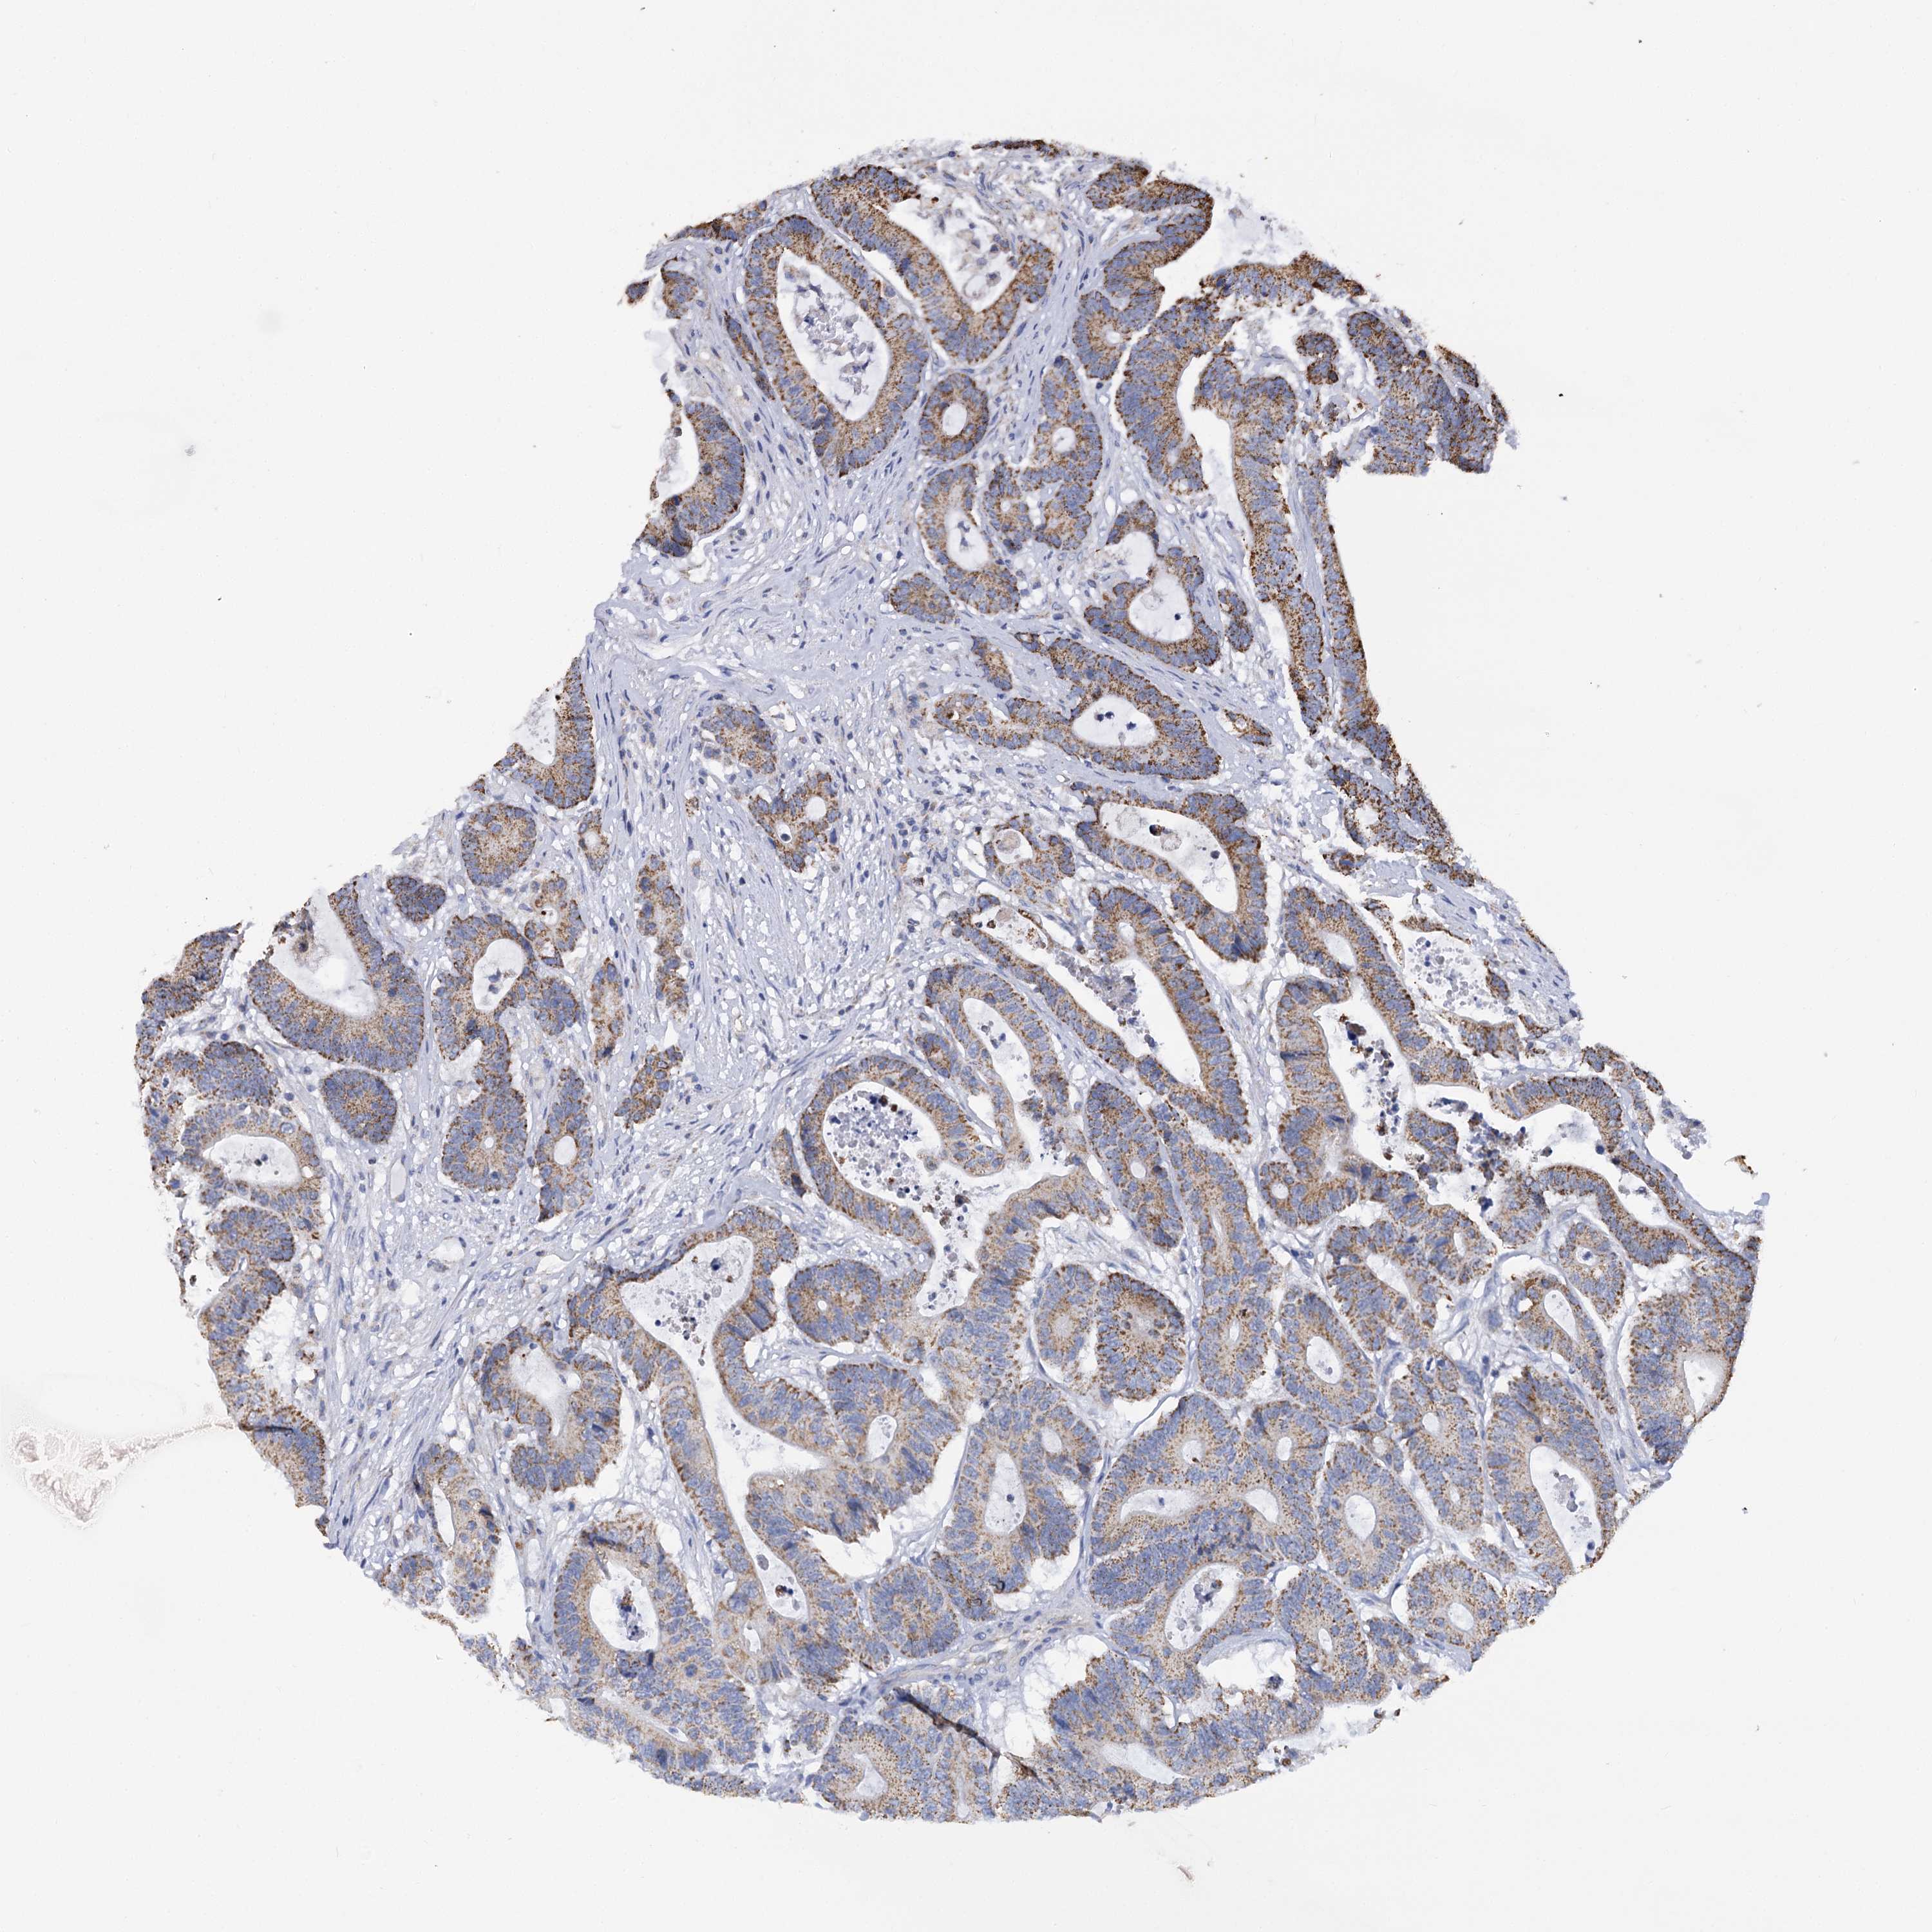

CANCER COLORECTAL CANCER Show tissue menu

Colorectal cancer

Human cancer

Colon adenocarcinoma